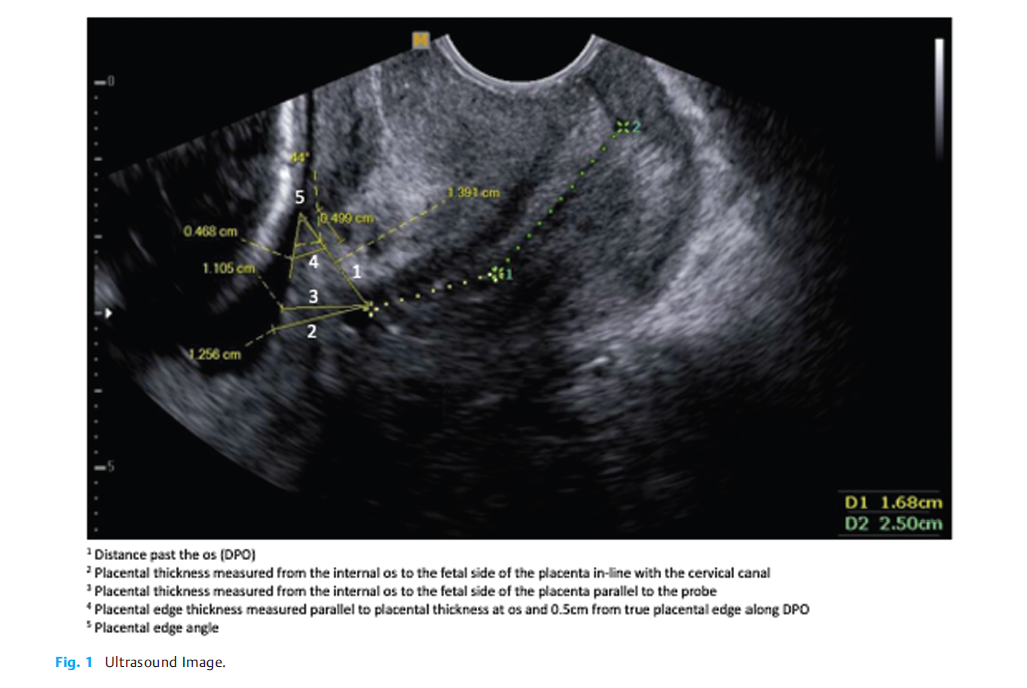

超声特征,见下图:

研究设计:本研究为一项回顾性队列研究。研究对象为妊娠16-27+6周超声诊断为前置胎盘的妇女。B超测量研究对象相关胎盘过宫颈内口的距离(DPO)、胎盘厚度、胎盘边缘角(PEA)、宫颈长度(CL)。收集研究对象体重、胎次、年龄、胎数、既往剖宫产次数、种族和吸烟情况等相关信息,同时了解胎盘位置、解剖超声时的胎龄、首次出血时的胎龄、分娩时的胎龄和分娩时的估计出血量。了解研究对象相关结局,进行统计学分析,进而了解前置胎盘超声特征与阴道出血的关系。